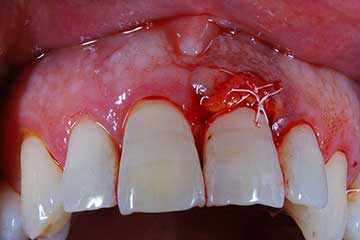

I denti irrecuperabili dell'arcata superiore ed inferiore del paziente di anni 65

sono stati sostituiti da 10 impianti, cioè protesi radicolari endo-ossee che sostengono le protesi fisse superiore ed inferiore.